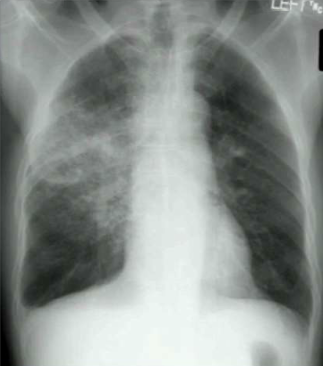

A child presents with T: 38, RR > 20, HR > 90 and WBC > 12,000. CXR is shown below. Blood cultures and sputum cultures are positive for gram + bacteria. What is causing his condition?

Septic shock. This is caused by local infection that then becomes bacteremic leading to sepsis (SIRS: systemic inflammatory response to infection) and shock. Note that septic shock kills 1/5 people.